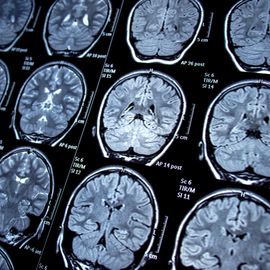

Neuroimaging

This page provides educational resources, events, news and products related to neuroimaging techniques and applications, including MRI, fMRI, CT, PET, DTI and MEG imaging in health and disease.